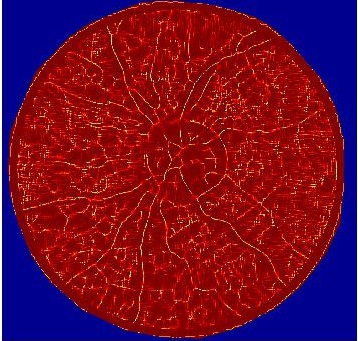

where balances the relative contribution of each feature. was experimentally set by varying it between in steps of and comparing the quality of the resulting SR images on a subset of images. The resulting saliency map in Figure 1 (e) clearly highlights the local retinal structures and thus justifies its use in the GAN cost function.

| (a) | (b) | (c) | (d) | (e) |

4.2 Retinal Blood Vessel Segmentation Results

We present retinal vessel segmentation results on the DRIVE [16], STARE [6] and CHASEDB1 [5] datasets with , and images respectively. Original images and manual annotations () are downsampled by to get and sets of from methods trained on [2]. and the sets of were used to train different state-of-the art U-Nets for vasculature segmentation [1]. The average accuracy () and sensitivity () for is summarized in Table 2. Better ISR methods should give higher vessel segmentation accuracy and performance of gives a lower bound on the segmentation error. ’s performance is closest to , and establishes its superiority over all competing methods. Figures 4 (a)-(h) show results of vessel segmentation on an example image. ’s performance is most similar to as is evident from the areas of inaccurate segmentation highlighted by yellow arrows. Most of the methods do not segment the finer vasculature structures, while SSR and SR-RF are unable to segment some of the major arteries.

| (a) | (b) | (c) | (d) | (e) | (f) | (g) | (h) |